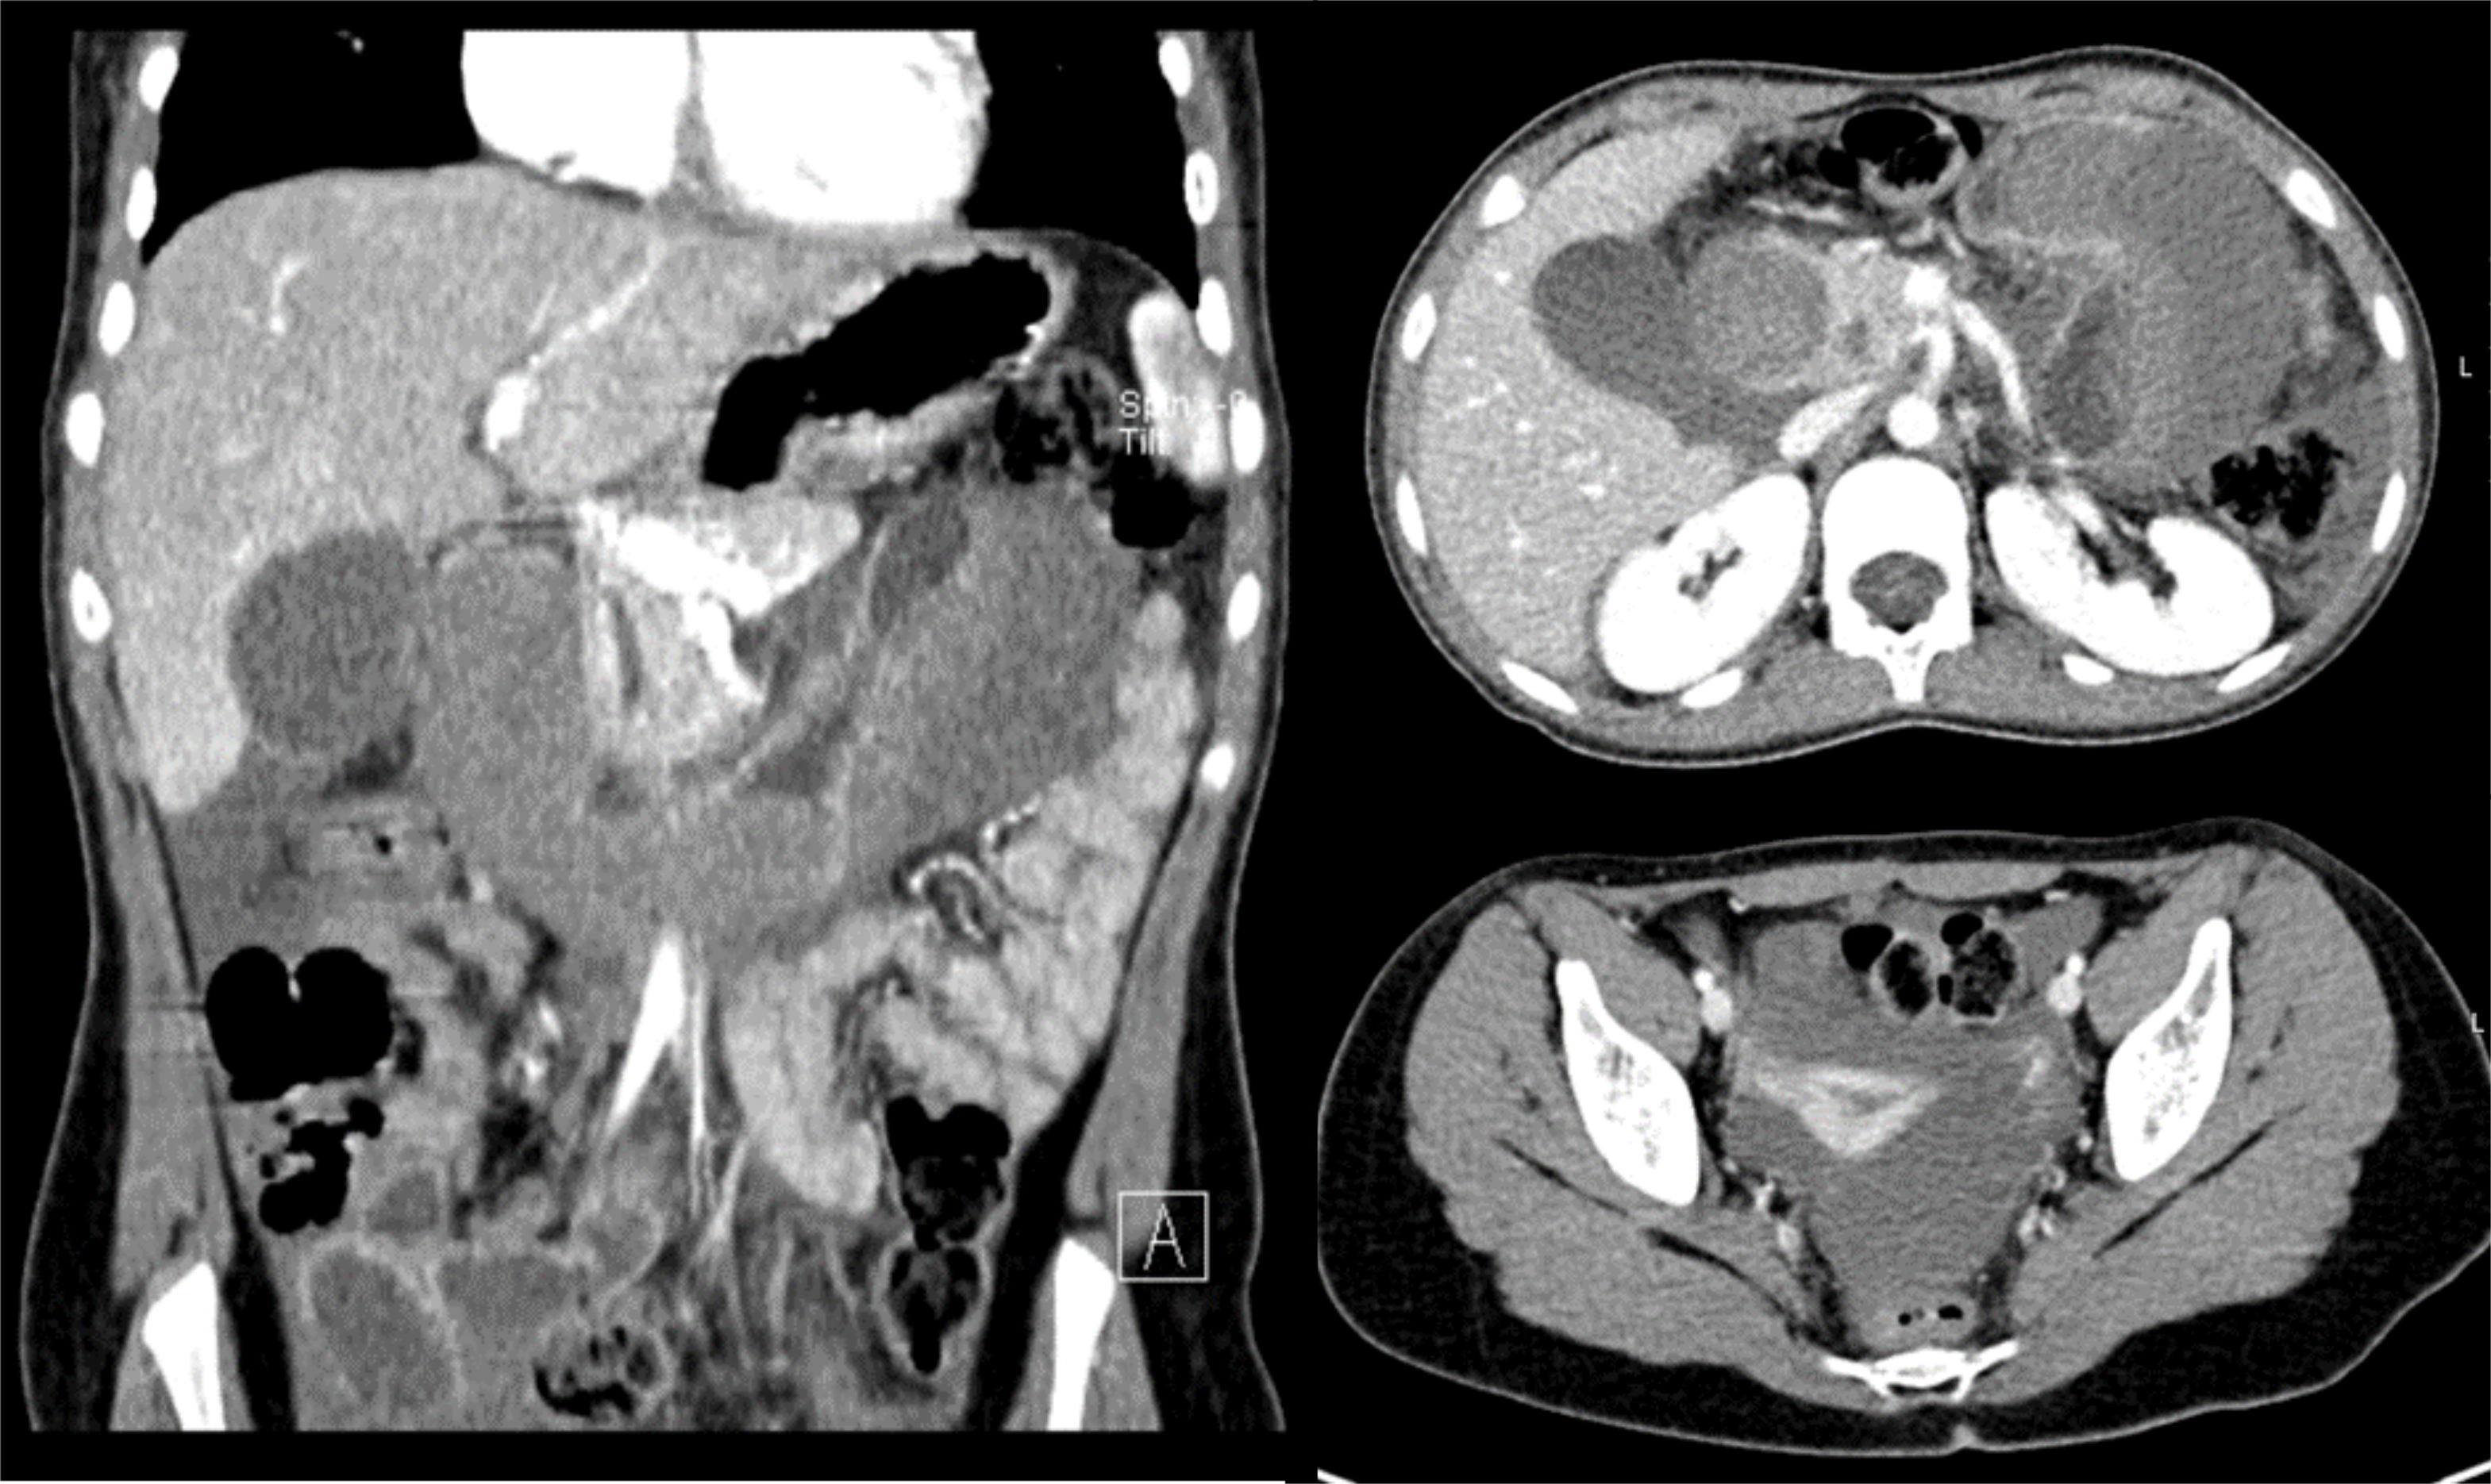

Duodenal hematoma is a rare complication of endoscopic duodenal biopsy, with just a few cases reported in children in the literature available.

The authors present a case of a 13 year-old girl, with a history of Noonan Syndrome and neurofibromatosis type 1, who presented abdominal pain and vomiting after an endoscopic duodenal biopsy.

In this article, we describe the clinical case, imaging findings, evolution and therapeutic approach.